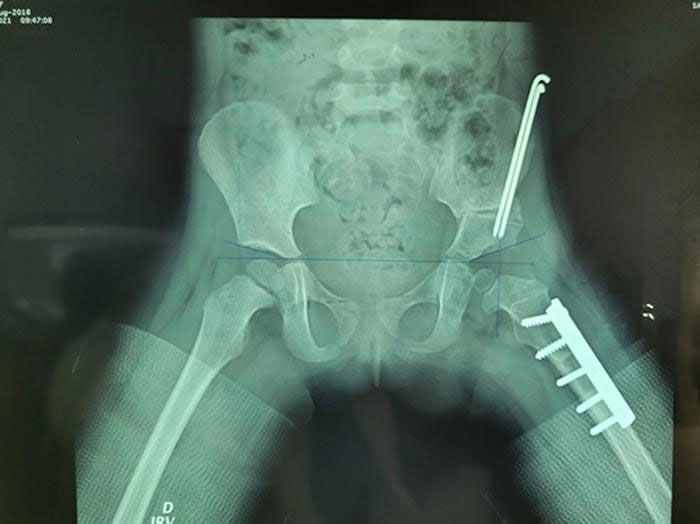

FRACTURA DE FÉMUR

- Ortopedia y Traumatología: Soluciones para fracturas, esguinces y otras lesiones traumáticas.